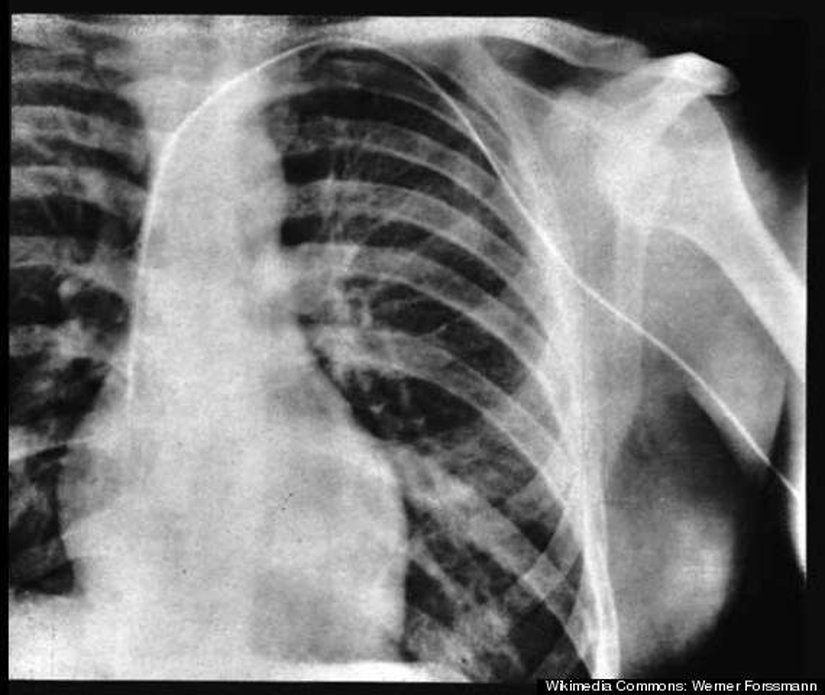

6. Werner Forssmann - Kendi Kalbine Kateter Takan Adam

Kardiyak kateterizasyon olarak bilinen tıbbi işlem günümüzde sıradan bir operasyon haline gelmiş olsa da, 20. yüzyılın başlarında yapılması son derece zor ve riskli bir işlemdi. Basitçe yapılan, kolda, boyunda veya karında açılan bir kesikten sokulan ince bir tüpün kalbe ulaştırılmasıdır. Bir zamanlar atan bir kalbe herhangi bir şekilde dokunmanın kalbi durduracağına inanılıyordu ve bu sebeple bu işlem akıl almaz geliyordu.

Werner Fossman ise tersine inanıyordu. Bunu ispatlamak için 1929 senesinde bu Alman bilim insanı kolunu uyuşturduktan sonra açtığı bir kesikten kateteri soktu ve kalbine kadar ulaştırdı. Kateterin istediği yere ulaştığından emin olmak için X-Ray taramasıyla kendisini kontrol etti. Deneyi tam bir başarıya ulaştı; ancak bu denemesi sebebiyle işinden oldu ve meslektaşları tarafından dışlandı. Neyse ki bilim camiası hakkını vermesini bildi ve 1956 yılında Nobel Ödülü'ne layık görüldü.